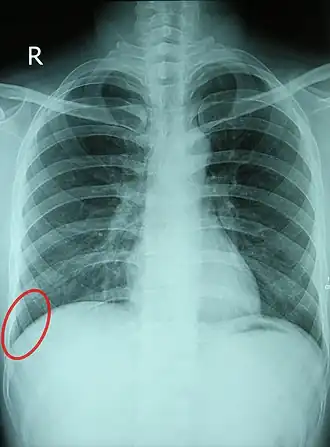

![]() Chest X-ray of a 30-year-old healthy man, with the costodiaphragmatic recess label in red ellipse | |

The costodiaphragmatic recess, also called the costophrenic recess or phrenicocostal sinus,[1] is the posterolateral fringe of the pleural space, a potential space around the lung inside the pleural cavity. It is located at the acutely angled junction ("reflection") between the costal and diaphragmatic parietal pleurae, and is interpreted two-dimensionally on plain X-rays as the costophrenic angle. It measures approximately 5 cm (2.0 in) vertically and extends from the eighth to the tenth rib along the mid-axillary line.

In anatomy, the costophrenic angles are the places where the diaphragm (-phrenic) meets the ribs (costo-).

Each costophrenic angle can normally be seen as on chest x-ray as a sharply-pointed, downward indentation (dark) between each hemi-diaphragm (white) and the adjacent chest wall (white). A small portion of each lung normally reaches into the costophrenic angle. The normal angle usually measures thirty degrees.